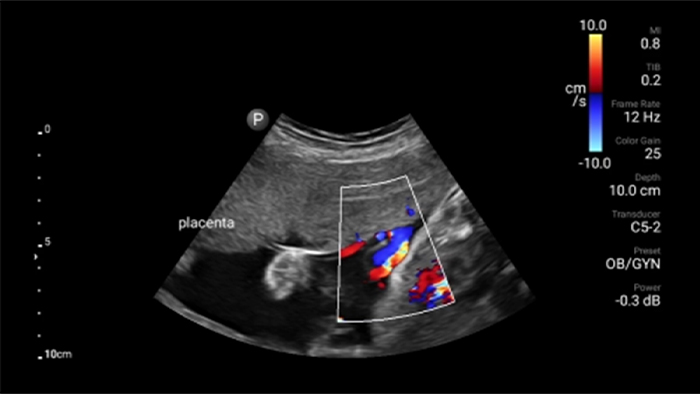

Lumify C5-2 broadband curved array transducer

• 5 to 2 MHz extended operating frequency range • 50mm radius of curvature • 2D, color Doppler, M-mode, advanced XRES and multivariate harmonic imaging, SonoCT • High-resolution imaging for deeper applications: abdominal, gall bladder, OB/GYN and lung imaging preset optimizations